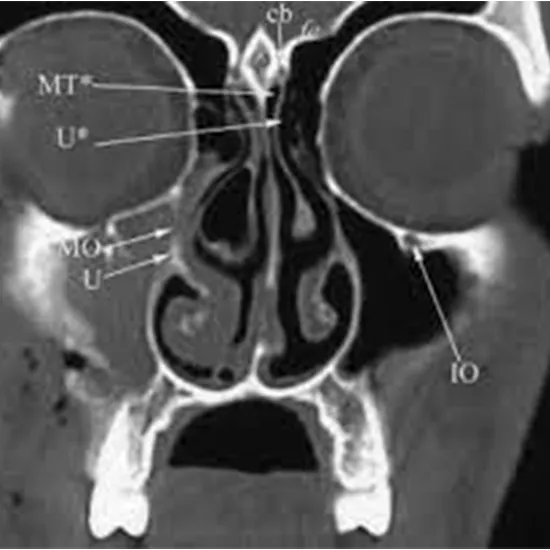

PNS(Para Nasal Sinus) are air-filled hollow spaces in the facial bones surrounding the nasal cavities. CECT PNS (Para-Nasal Sinus) Axial is contrast-enhanced computed tomography of para nasal sinus. It is an imaging procedure that involves an X-ray beam and contrast media to obtain pictures of the paranasal sinus.

CECT PNS axial uses the contrast material for the detection of abnormalities in the PNS. The patient is administered with contrast material and allowed to wait for at least 1 hour so that the medication reaches the scanning area. The CT scan usually works by using several X-ray beams and also by using electronic X-ray detectors that are rotating around the patient. A special computer will also be used to generate two-dimensional cross-sectional images of the patient’s body.

CECT PNS Axial test scan shows inflammation, infection, fractures, injuries, tumours etc. in the paranasal sinus.